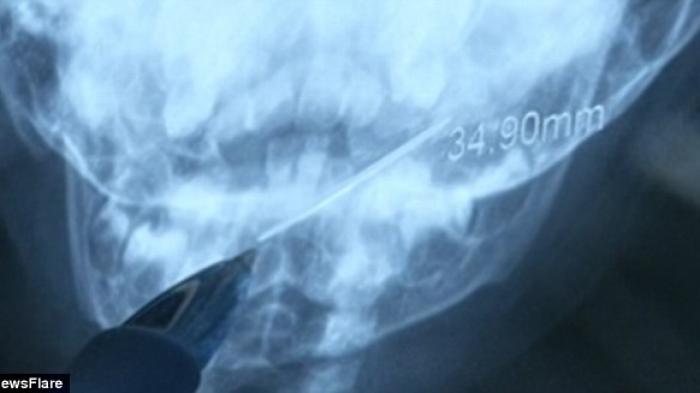

Jarum sepanjang 4 sentimeter tertelan, hingga tersangkut di kerongkongan seorang bayi perempuan berusia satu tahun.

Upaya penyelamatan bayi tersebut direkam dalam video. Tampak para dokter menunjuk ke bayangan jarum lewat sinar x. Jarum itu tersangkut di kerongkongan.

"Jarum itu panjangnya 4 sentimeter dan satu ujungnya menusuk tonsil," kata seorang dokter.

"Sedangkan ujung lainnya di dasar kerongkongan. Jika tidak dikeluarkan segera, mungkin akan menyebabkan pendarahan atau infeksi," lanjutnya.